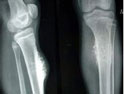

骨纖維肉瘤是起源于非成骨性纖維結(jié)締組織的一種少見惡性骨肉瘤,也是纖維源性惡性腫瘤。好發(fā)于四肢長骨干骺端或骨干,以股骨多見。原發(fā)于骨髓腔內(nèi)結(jié)締組織者,稱為中央型骨纖維肉瘤,較多見。原發(fā)于骨膜的纖維組織者,稱為周圍型骨纖維肉瘤,較少見。繼發(fā)性骨纖維肉瘤,常繼發(fā)于原有骨病,如畸形性骨炎、骨纖維異樣增殖癥、動脈瘤樣骨囊腫、慢性骨髓炎、復(fù)發(fā)的骨巨細胞瘤等。